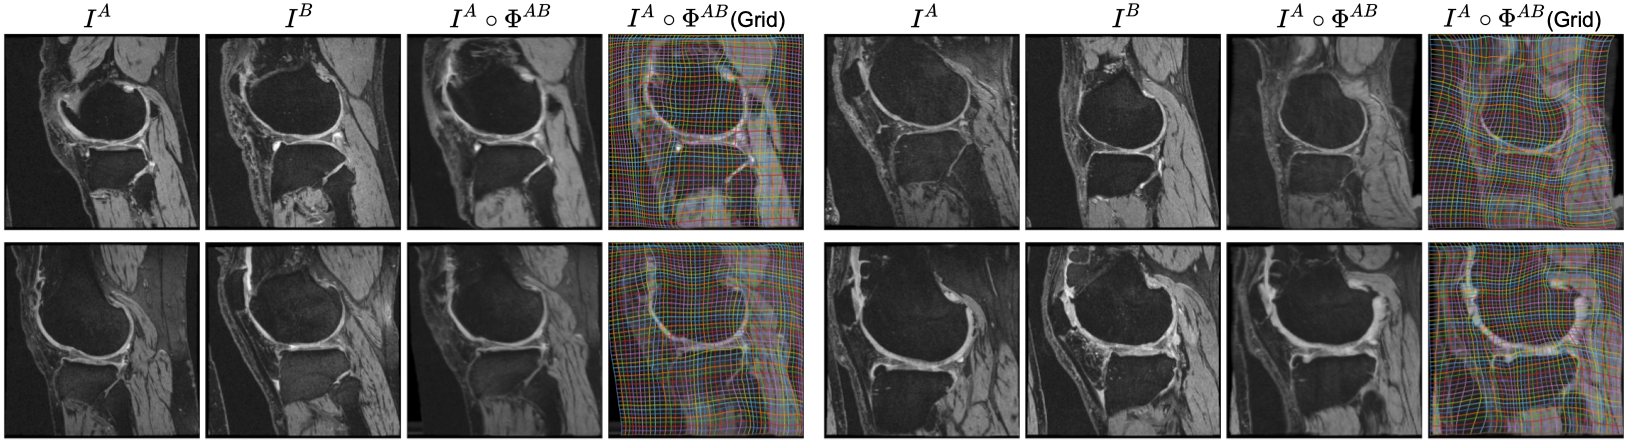

To run our pretrained model in the cloud on 4 sample image pairs from OAI knees (as above), visit our google colab notebook